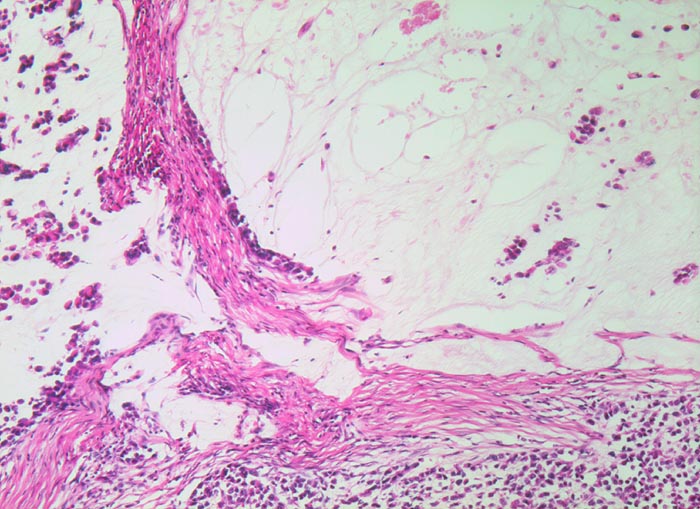

Der invasive Karzinomanteil zeigt teilweise muzinöse Differenzierung (teils siegelringzellige Tumorzellen schwimmen in extrazellulären Schleimseen).

Tumorfreie Lamina muscularis propria.